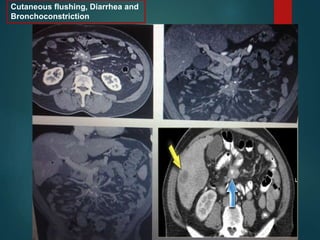

Carcinoid…

Cutaneous flushing, Diarrhea and

Bronchoconstriction

Carcinoid… • Slow-growing neuroendocrinetumor most commonly found in the small bowel. • Metastasizes to the mesentery • Associated bowel wall thickening due to a desmoplastic reaction.

Cutaneous flushing, Diarrheaand Bronchoconstriction

• #37 • Less than 10% of patients with carcinoid will develop the carcinoid syndrome, caused by the overproduction of serotonin, which can lead to symptoms of cutaneous flushing, diarrhea and bronchoconstriction.

• #38 Metastatic carcinoid tumor. A: Transaxial computed tomography shows a lobulated soft tissue mass (arrow) with punctate central calcifications at the root of the small bowel mesentery. Strands of soft tissue density radiating from the mass toward the small bowel loops are indicative of desmoplastic response to the tumor. B: Coronal image also demonstrates the characteristic features of the mass. C: Coronal maximum intensity projection (MIP) image shows engorgement of the mesenteric veins due to partial obstruction by the mass. Note the large hepatic metastasis (arrowhead carcinoid with centra calcification. Notice the bowel rteaction and wall thickening. Also a liver mets

• #41 On the left a 33-year-old man who complains of an increasing abdominal girth, abdominal fullness, and a palpable abdominal mass. First study the images on the left and continue with the MR. Look for some imaging features that are helpful in the differential diagnosis. Mesenteric fibromatosis or desmoid is a benign proliferative process that is locally aggressive and can recur, but it does not metastasize. The small bowel mesentery is the most common site. 13% of patients have familial adenomatous polyposis (FAP). On the left images of another patient with mesenteric fibromatosis. Notice that this lesion is not of low attenuation. This lesion has a more collagenous or fibrous stroma. So there are two distinct patterns